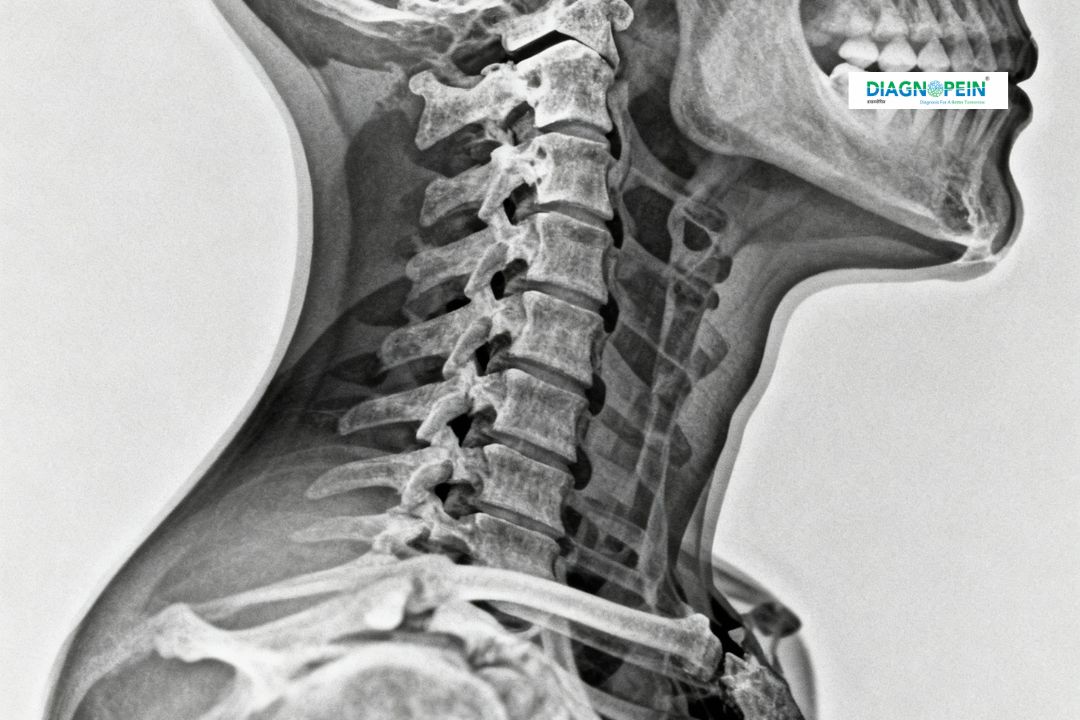

An X-Ray Cervical Spine AP/LAT is a specialized diagnostic imaging test that captures clear images of the upper portion of your spine — from the neck to the upper back. The two standard views, Anteroposterior (AP) and Lateral (LAT), help doctors assess bone alignment, joint spacing, and any structural problems in the cervical vertebrae. At Diagnopein in karad, we offer advanced imaging with digital X-ray technology ensuring quick, accurate, and low-radiation results for every patient.

This test is commonly prescribed for patients experiencing neck pain, stiffness, numbness, tingling in the arms, or after injuries like falls or whiplash. The imaging helps detect degenerative diseases, bone spurs, disc issues, or fractures of the cervical region.

An X-Ray Cervical Spine AP/LAT plays a crucial role in identifying causes of chronic neck pain and in planning appropriate treatments. The cervical spine supports the head, allowing movement while protecting the spinal cord. Even small issues here can cause significant discomfort or neurological symptoms. This test gives doctors a detailed view of the vertebrae's alignment and spacing.

1. Alignment of the cervical vertebrae (C1–C7)

2. Disc space and bone density

3. Curvature or any abnormal angulation

4. Signs of spondylosis, fractures, or degenerative changes

5. Evidence of foreign bodies or structural deformity